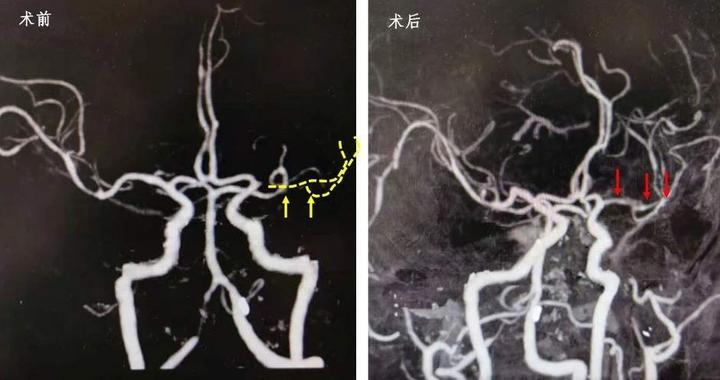

2、左侧MCA原有闭塞的解剖结构重新开放